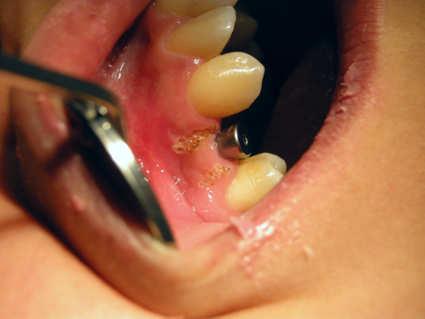

Sialolithiasis refers to the formation of stones in the salivary glands. Stones are most commonly found in the submandibular gland, where stones can obstruct Wharton's duct. It is frequently associated with chronic infection (Staphylococcus aureus, Streptococcus viridans) of the glands, dehydration (phenothiazines), Sjögren's syndrome and/or increased local levels of calcium, but in many cases can arise idiopathically. Pain, when present, usually originates from the floor of the mouth, although in many cases the stones cause only intermittent swelling.

Since chewing promotes release of saliva, symptoms tend to increase during meals. A palpable lump or visible swelling in the area of the gland is often noted.

Complications include persistent obstruction of the duct, leading to bacterial invasion, overgrowth and infection (sialoadenitis). This can require IV antibiotics such as nafcillin, and sometimes surgical drainage.